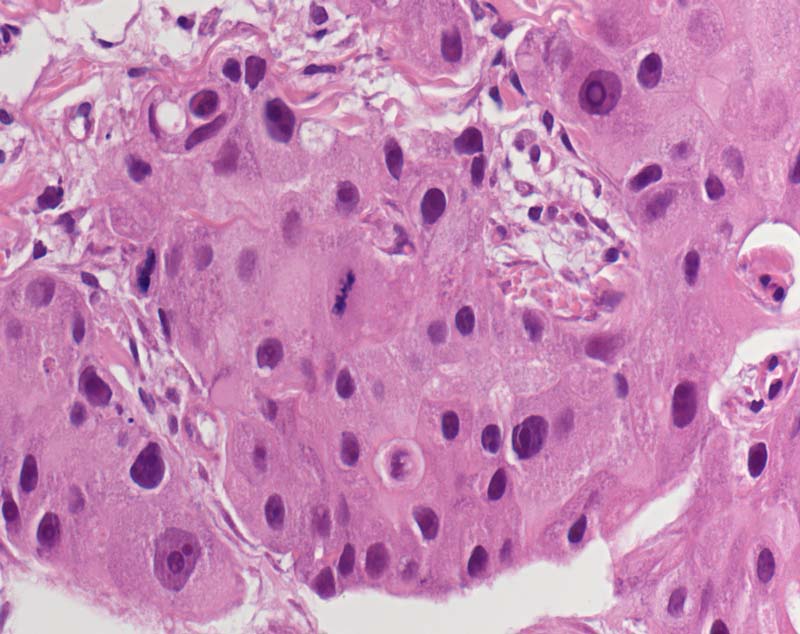

PathoPic – image database / PathoPic ID 8051 - mässig differenziertes invasives apokrines Karzinom

mässig differenziertes invasives apokrines Karzinom

maligner Tumor

Mamma

Solider Tumor bestehend aus stark atypischen Tumorzellen mit reichlich eosinophilem Zytoplasma und polymorphen Tumorzellkernen mit prominenten eosinophilen Nukleolen. Mitose.

G2 (B.R.E. Score 7), ER negativ, PR negativ, HER-2/neu negativ.

Mammakarzinom cT4.

Histologie

400